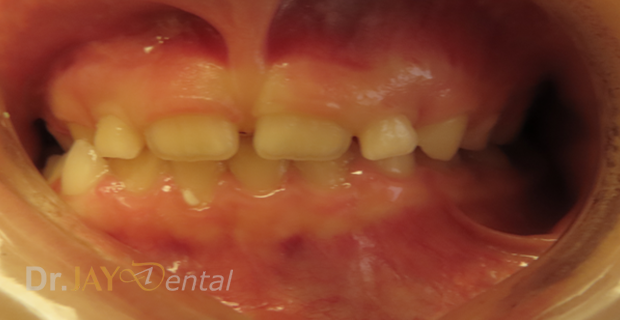

CASE 4

Early intervention plays a big role, the kid was 7yrs old, we started treating her early, helped facilitate her growth and wider palate helping her sleep better as she had good airway. Patient was having night terrors and sleep disturbances along with snoring. The treatment change was in 4 months.